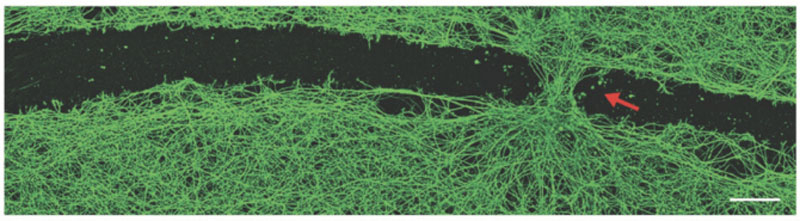

Em seu experimento, os cientistas colocaram um grupo de antroporobôs produzidos dessa forma em um corte simulado de tecido neural. A observação mostrou que logo apareceu uma ponte no corte entre suas bordas e a “ferida” cresceu em poucos dias. Os cientistas não conseguem explicar o mecanismo e a biofísica do fenômeno, mas consideram a experiência encorajadora e pretendem continuá-la. Isto corresponde aproximadamente ao comentário popular sobre notícias científicas no nosso site: “Nada está claro, mas muito interessante”. Muitos ficarão surpresos, mas a grande ciência também começa muitas vezes por se mover numa direção desconhecida.